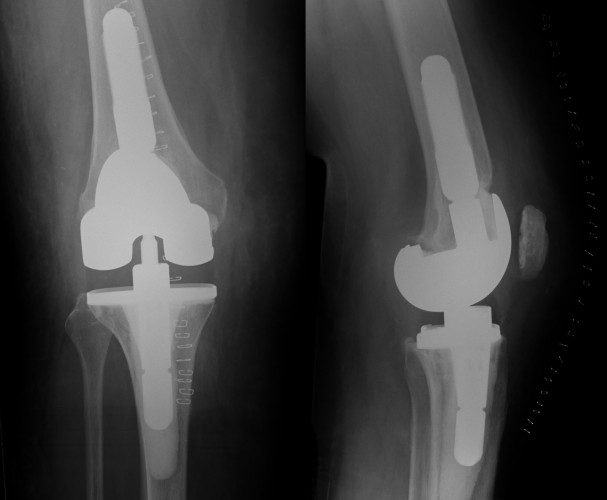

Considering a Total Knee Replacement? Howard J. Luks, MD